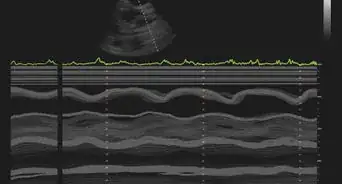

- Go to your doctor for a diagnosis. They will give you a physical exam and then decide whether to do blood tests or imaging tests.